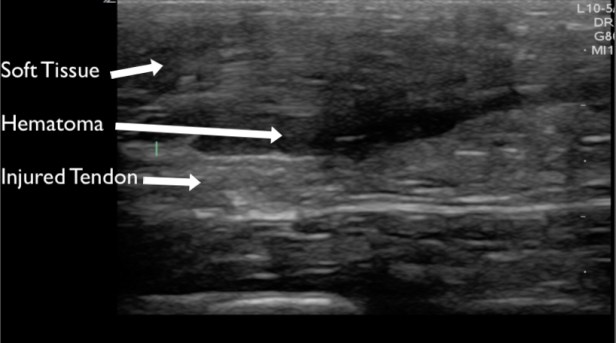

Tendons should be interrogated in their entirety in the short and long axis to where they insert into the bone. The region adjacent to bony insertion is where the majority of pathology is identified. Complete or partial ruptures are readily apparent as disruption of normal striated tendon fibers often with associated surrounding hematoma (Figures 11, 12 & 13). Range of motion testing with simultaneous ultrasound can assist in evaluation for complete ruptures. Tendinopathy can be identified by the presence of calcifications (Figure 14), edema (Figure 15), and increased vascularity (when compared to the contralateral tendon). Edema will make the tendon more hypoechoic and larger in diameter compared to the contralateral tendon.

Figure 11. The Achilles tendon evaluated in the long axis demonstrating a partial or complete rupture with adjacent hematoma.